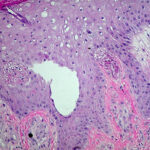

Histopathology . Pyoderma gangrenosum exhibits a dichotomous tissue reaction, showing central necrotizing suppurative inflammation, usually with ulceration, and a peripheral lymphocytic vascular reaction comprising perivascular and intramural lymphocytic infiltrates, usually without fibrin deposition or mural necrosis . Transitional areas show neutrophils in a loose cuff around the angiocentric lymphocytic infiltrates, defining a mixed lymphocytic and neutrophilic vascular reaction termed a Sweet’s-Iike vascular reaction . Bullous lesions may also demonstrate a Sweet’s-like vascular reaction with perivascular disintegrating neutrophilic infiltrates and hemorrhage without mural necrosis or luminal fibrin deposition. At variance with Sweet’s syndrome is destruction of the connective tissue framework with resultant tissue pathergy . Although a leukocytoclastic vasculitis may be observed in areas of maximal tissue pathology, pyoderma gangrenosum does not reflect a primary vasculitis . In some cases a necrotizing pustular follicular reaction may be the central nidus of the lesion, particularly in the vesicular pustular variant associated with ulcerative colitis or hepatobiliary disease. In the superficial granulomatous variant, florid pseudoepitheliomatous hyperplasia may be observed along with the intraepithelial and superficial dermal suppurative granulomatous inflammation with admixed plasma cells and eosinophils . Gases of pyoderma gangrenosum associated with Grohn’s disease may have areas of granulomatous inflammation . |